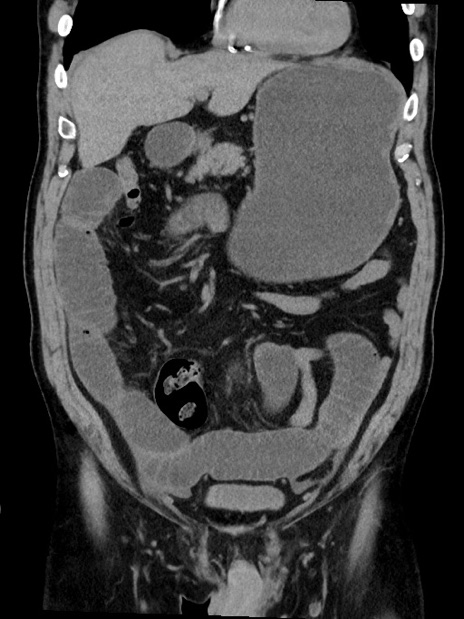

症例35(冠状断像)

【症例】70歳代 男性

【主訴】腹部膨満、嘔吐

【現病歴】昨日より腹部膨満感出現。本日増悪し、仙痛出現。嘔吐あり、受診。

【既往歴】糖尿病、胆摘後

【身体所見】BP 149/80mmHg、HR 74/min、BT 35.9℃、腹部:膨満、軟、圧痛なし。腸雑音減弱あり。上腹部正中切開瘢痕あり。

【データ】WBC 13500、CRP 1.72